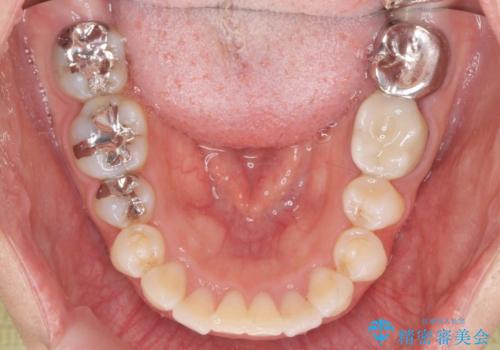

前歯の角度を改善するマウスピース矯正

しっかりと拡大を行い、IPRも併用したことで歯並びと前歯の角度を大幅に改善することができました。